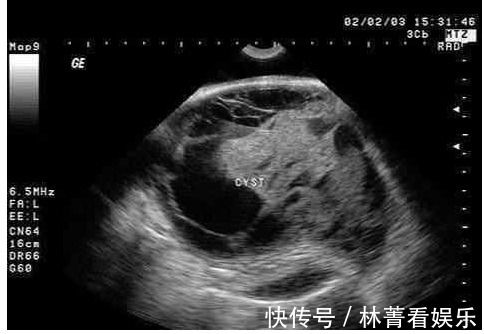

天下之大无奇不有。总有些奇怪的事跟奇怪的人能让人感到意外。小编将给你提供各种奇闻异事。希望大家喜欢,如果给你点意外跟惊喜的话就点个赞。今天又为大家带来了不一样的内容,相信大家期待了很久吧!每天为大家进行内容推送,希望远方的你们都能关注到!刘女士在怀孕期间都按时产检,可是在四维检查时候医生发现胎儿的臀部有一个巨大的肿瘤,医院建议刘女士放弃这个孩子,可是她还是坚持要生下来。

到了35周的时候,宝宝来到了这个世上,属于早产儿,是个女孩,爸爸妈妈都高兴不起来,因为孩子的肿瘤比她的头还大,这让医生感觉很棘手,出生2天后只能转院去专门的肿瘤医院治疗了。

孩子接受了肿瘤切除和初步整形手术,手术时间长达8个小时。这个手术除了要切除肿瘤外,还要控制好手术出血等问题,手术难度非常大。

目前孩子虽然还在温箱中,但已撤除呼吸机,伤口基本愈合,生命体征平稳,后期还需要进行观察。医生解释这个畸胎瘤病因目前还不明确,但跟胚胎期人体多能干细胞(生殖细胞)异常分化有关。医生提醒:从妊娠早期开始,孕妇要避免病毒感染,避免接触有毒物等生物、化学和物理致癌因素,保持良好的生活习惯等,做好孕前检查、产前检查,发现问题及时治疗。今天小编给大家带来的小新闻就结束了,大家如果喜欢小编的话了,一定要记得给小编点点关注,顺便给小编点个赞,给小编更多的动力,以激发小编给你们带来更多好的文章。还有记得在下方多多评论,和你们可爱的小编多探讨探讨!